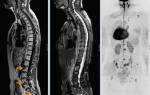

- Развитие метастазов в костях позвоночника. Характерно для рака желудка.

- На третьем этапе наблюдается развитие необратимых процессов. Болезнь прогрессирует. Начинается метастазирование в ближайшие органы. Характер болей при метастазах изменяется. Сильные, постоянные и длительные – характерные проявления третьей стадии онкологии. Болевые ощущения локализуются там, где произошел выброс метастазов.

Распространение метастазов в лимфоузлы

Наличие болей в спине указывает на метастазирование патологии и вовлечение либо железы, либо тканей позвоночного столба.